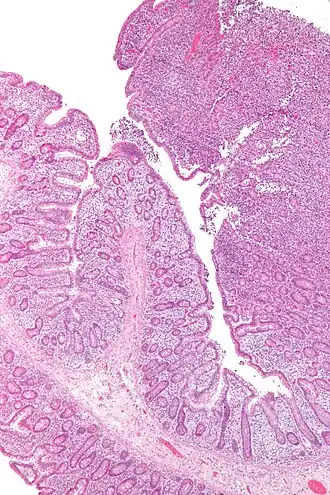

![]() Una micrografía del linfoma de células T asociado a enteropatía. | ||

Es causada por la activación de un gen mediada a través de la proteína viral P40 de las HTLV-1. La apariencia de las células de este tumor varía con amplitud: típicamente son células de núcleo multilobulado descrito como células en forma de coliflor, con frecuencia encontradas en tejidos involucrados como la piel, médula ósea y en sangre periférica. Aunque menos habitual, también están presentes células gigantes multinucleadas, que recuerdan las células Reed-Sternberg. Y un número variable de linfocitos malignos CD4+ en la sangre periférica. Las células de este tumor contienen provirus HTLV-1 clonal compatible con el involucro directo patogénico del virus en este neoplasma, además expresan altos niveles de CD25 en la cadena α de receptores para interleucina-2 (IL-2). Las células T en el linfoma expresan CD2, CD3 y CD5. La mayoría de los pacientes tienen células T colaboradoras del tipo inmunológico (CD4+).